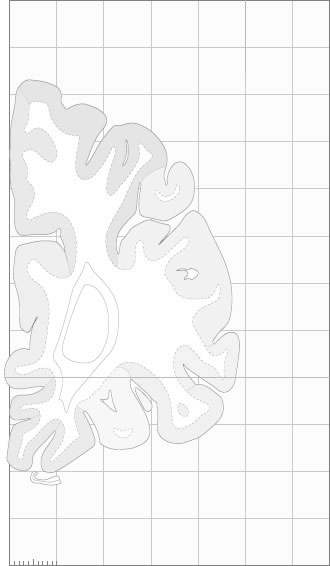

Frontal sections (Nissl) from the Atlas Brain:

Schematic

Slice ID:

r1-0050

Plate NR:

05

Position:

-34,5 mm